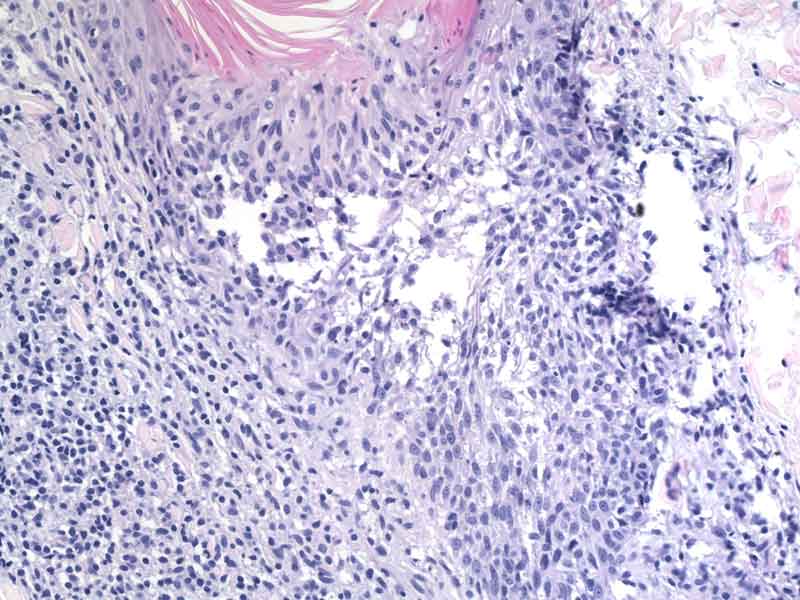

“Per studiare queste malattie abbiamo usato un modello murino in cui abbiamo cercato di curare l’infezione da Trichuris muris, un verme strettamente affine all’equivalente umano, Trichuris trichiura.”

“Dapprima abbiamo scoperto che i topi che erano in grado di espellere i parassiti producevano più muco e che il muco di questi topi conteneva mucina Muc5ac. Si tratta di una mucina che raramente si trova nell’intestino, ma che quando è presente altera le proprietà fisiche del gel di muco.

Successivamente abbiamo studiati topi geneticamente incapaci di produrre la Muc5ac, scoprendo che essi non erano in grado di espellere i vermi anche se avevano una forte risposta immunitaria contro i parassiti. E questo portava a un’infestazione di lungo periodo”, ha aggiunto Richard Grencis, co-autore dello studio.